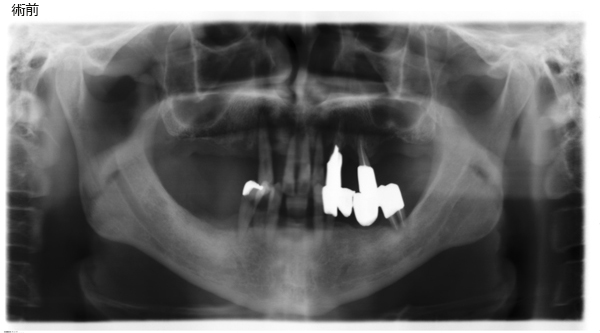

⑮ガイデットサージェリー(前顎に及ぶ歯槽骨非薄)